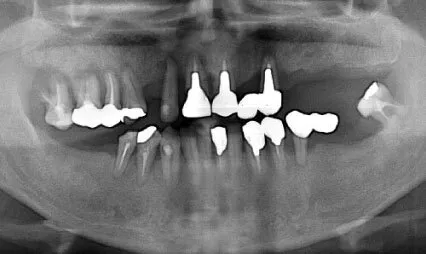

症例②

| 主訴 | 食事ができない |

|---|---|

| 診断名 | 咀嚼障害 |

| 年齢 | 58歳 |

治療に用いた装置(治療法) | 上顎:オールオン6 |

| 部位 | 上顎:右上7・右上5・右上2・左上4・左上5・左上6 下顎:右下7・右下6・左下5・左下6・左下7 |

| 治療期間 | 1年 |

| 治療費用 | 上顎:3,800,000円 下顎:2,310,000円 |

| リスク・副作用(治療に関する) | 腫脹しびれ |